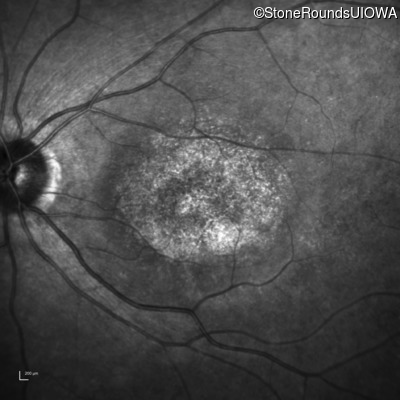

Infrared Fundus Photograph - Right - 20/200 -3

Exemplar

Infrared Fundus Photograph - Left - 20/200 -2